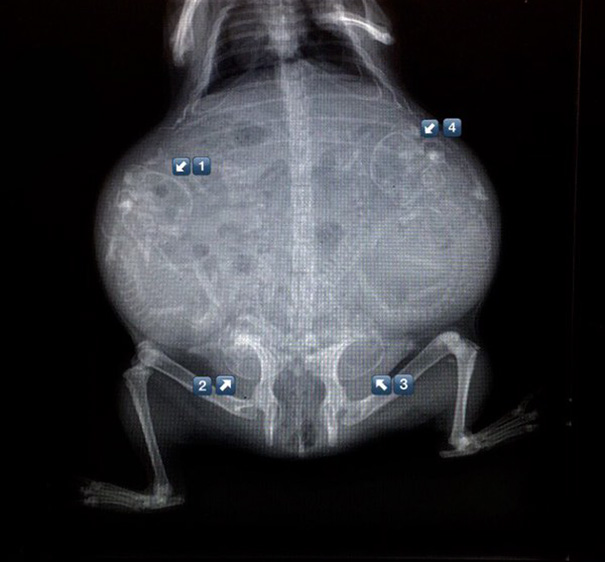

Unikāli rentgena attēli ar dzīvniekiem gaidībās

Bieži negadās publiski redzēt dzīvnieku rentgena uzņēmumus. Turklāt šie rentgena uzņēmumi ir veikti dzīvniekiem, kuri ir mazuļu gaidībās. Tagad ikvienam ir iespēja ielūkoties, kā dzīvnieku mazuļi attīstās savu mammu vēderos.